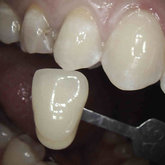

Porcelain crowns and restorations made in one appointment.

We make it a priority to incorporate the latest in dental technology in everything we do at our practice. ...